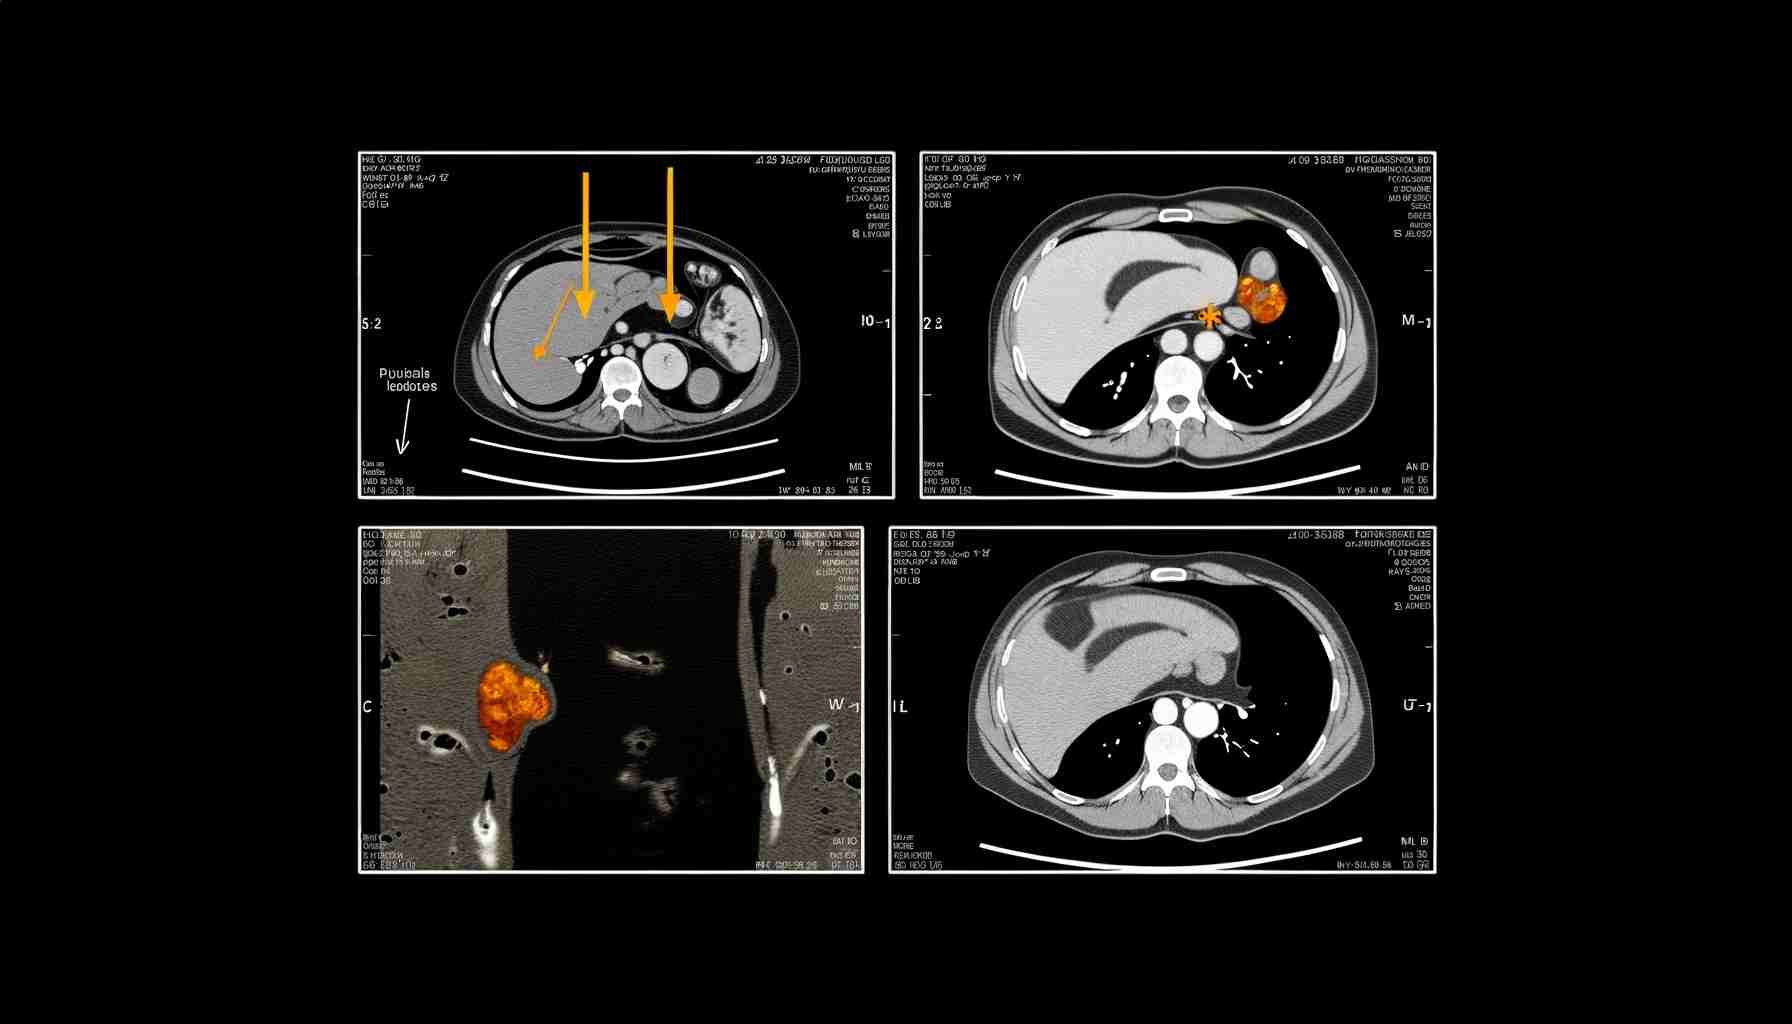

Нейробластома забрюшинного пространства у детей

Нейробластома забрюшинного пространства у детей – это злокачественная опухоль, которая диагностируется в 97% случаях у пациентов, не достигших 15-летнего возраста, из них – это 85-90% дети до 5-ти лет. Чаще заболевание выявляется у мальчиков, чем у девочек. С возрастом риск развития злокачественных процессов становится ниже. Выздоровление возможно при ранней диагностике и правильной комплексной терапии.

• УЗИ брюшной полости, КТ и МРТ;

• позитронно-эмиссионная компьютерная томографииюя (ПЭТ-КТ).